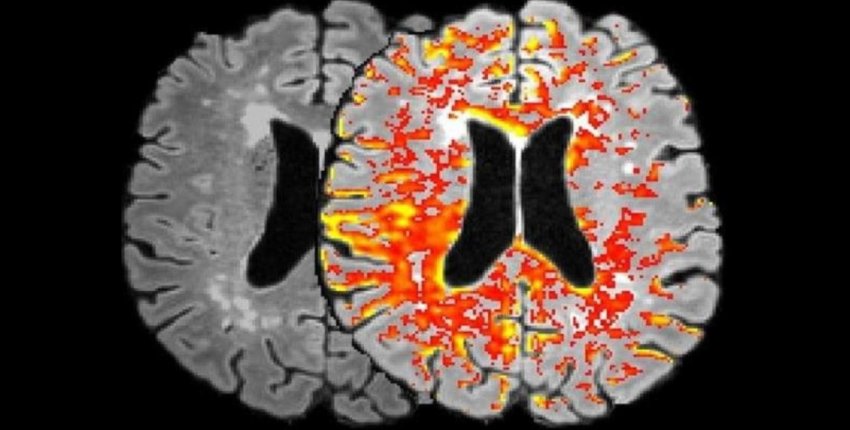

L'anticorpo terapeutico della fibrina è entrato nel cervello, si è accumulato in aree ricche di fibrina e ha protetto dalla neuroinfiammazione e dalla neurodegenerazione entrambi i modelli di malattia. L'analisi molecolare ha mostrato che il trattamento riduce anche l'attivazione di percorsi biochimici che contribuiscono all'infiammazione e allo stress ossidativo, una potenziale fonte di molecole che possono avvelenare le cellule, inclusi i neuroni.

Nel topo modello di Alzheimer, gli animali sono stati trattati con l'anticorpo dopo aver già sviluppato accumuli di proteine amiloidi nel cervello, un segno distintivo della malattia. Rispetto ai topi trattati con placebo, i topi trattati con l'anticorpo hanno avuto meno infiammazione del cervello e hanno perso meno neuroni.

Allo stesso modo, il trattamento con l'anticorpo ha ridotto l'attivazione delle cellule infiammatorie e il loro accumulo nei siti di infiammazione nel topo modello di sclerosi multipla. Inoltre, ha ridotto la perdita di assoni nervosi, che spesso degenerano nei pazienti con sclerosi multipla.